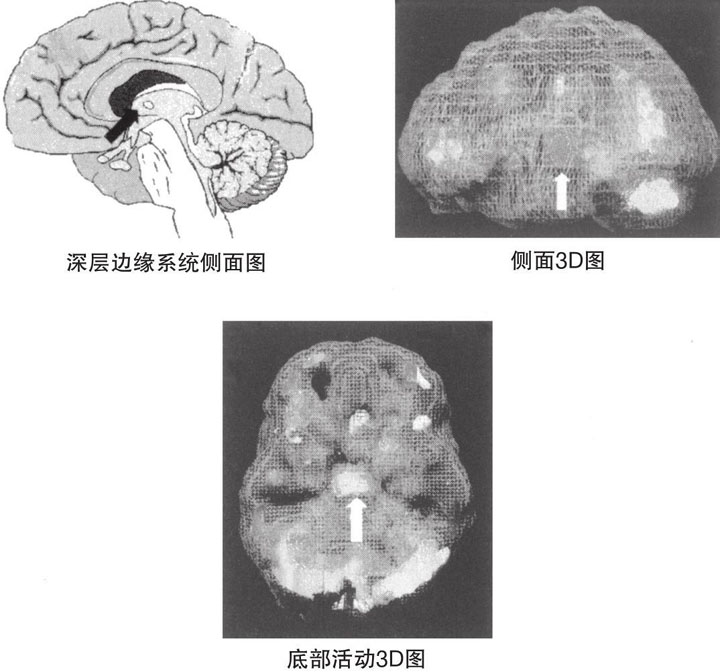

图2-1 深层边缘系统

图2-2 萨拉受到躁狂抑郁症影响的大脑3D图

要对她进行脑部扫描并不是一件容易的事。临床大夫尝试了三次。前两次她都拔掉了静脉注射管,并大声说我们想毒死她。第三次,她的妹妹和她交谈后令她放松下来,这一次终于成功了。当扫描结果显示出她的深层边缘系统整体上存在过度激活时,我发现她左侧的大脑激活程度更高,即深层边缘系统有非常集中的焦点,并且整个大脑皮层都出现了明显的斑驳亮点(见图2-2)。换句话说,萨拉的一部分脑区显示出了过度激活,而另一部分脑区则呈现出抑制的状况。经验告诉我,周期性心境障碍通常都会和这种情况有关。